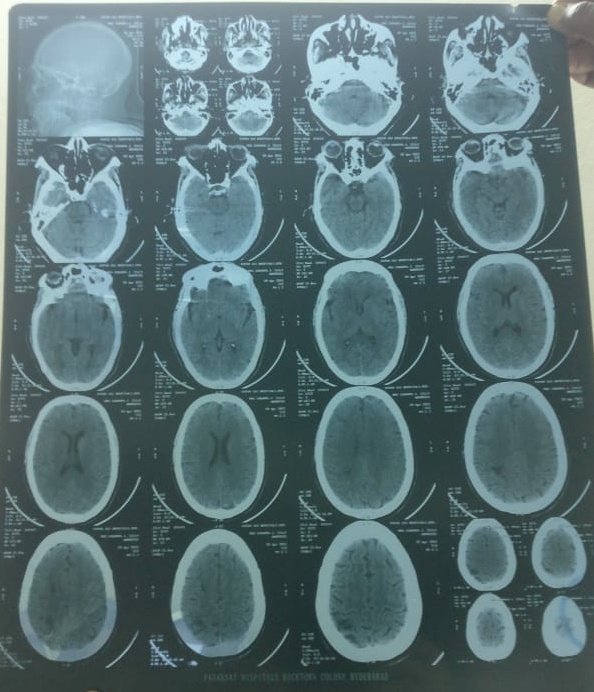

Investigations:-

Ultrasonography finding- Renal parenchymal disease of grade- 2.

Provisional Diagnosis: Chronic Kidney Disease etiology- secondary to systemic Hypertension.